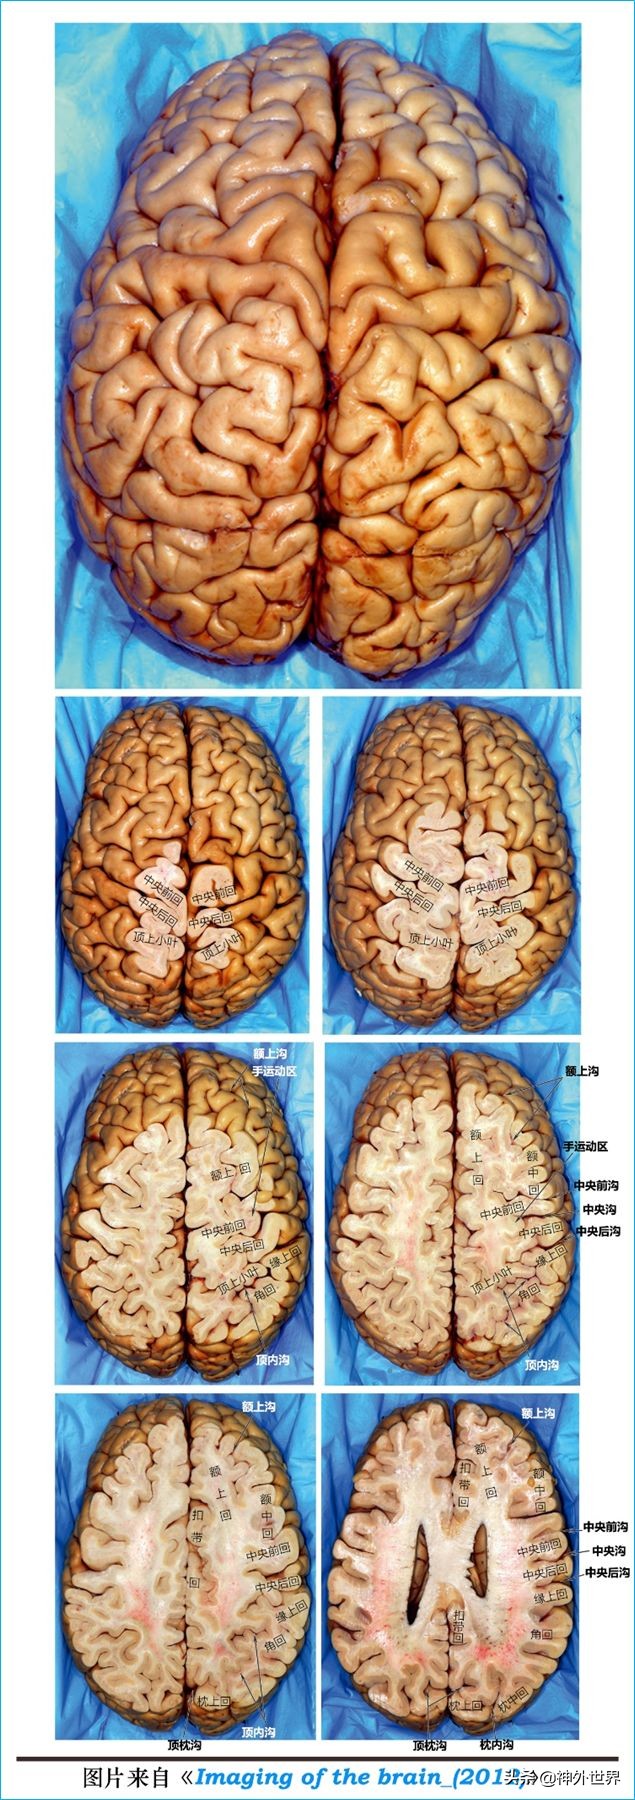

1、上面观识别脑沟和脑回:

三、大脑半球标本连续切片学习断层

1、水平位连续切片